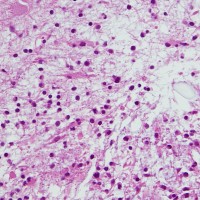

思春期のまだ増大している毛様細胞性星細胞腫

17歳です。間質に富む疎な部分は増大傾向を示しT1ガドリニウム増強される部分です。一方で,増強されない部分では,MRIで増大傾向がなく,病理では組織がコンパクトとなり,HEでは星細胞腫グレード2のよう見えます。

思春期に入って退縮期に入った毛様細胞性星細胞腫の組織像

13歳思春期の毛様細胞性星細胞腫です。angiocentric patternも失って,粘液基質が少なくなって,ローゼンタール線維が豊富になっています。(びまん性)星細胞腫グレード2と誤診されることが多く,核の大小不同も目立ってくると(退形成性)星細胞腫 グレード3と病理誤診されることもあります。